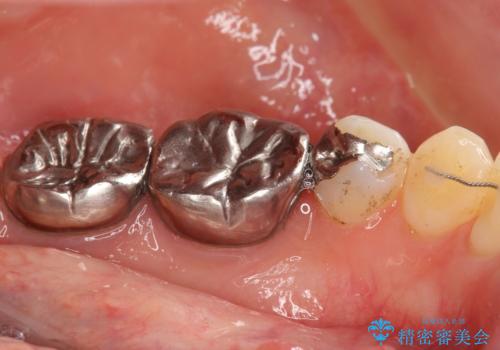

- 低予算で銀歯を白くしたいとご希望し来院された患者様です。

右上小臼歯(右上5)はオールセラミッククラウン(e-max press)、下顎臼歯(下顎両側67)はメタルボンドクラウンによりやりかえることにしました。

再根管治療はご希望されず、行っておりません。